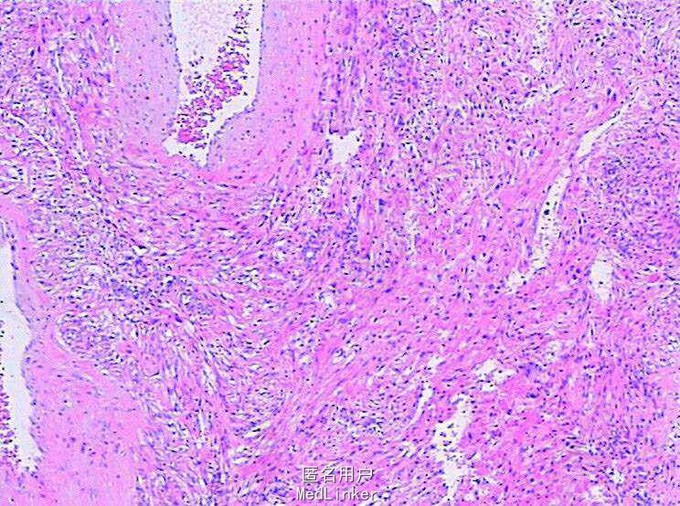

诊断:肾错构瘤 在全麻下行“后腹腔镜左肾部分切除术+肾周粘连松解术”,术程顺利,术后恢复好。

构瘤亦名肾血管平滑肌脂肪瘤,是良性肿瘤。国外报告大约50%诊断肾错构瘤病人有结节性硬化,是一种遗传性疾病,并有家族发病倾向,表现为大脑发育不良、癫痫、面颊部皮脂腺瘤。错构瘤也可发生在脑、眼、心、肺、骨,有时可误认为转移病灶。我国肾错构瘤病人合并结节性硬化者比较少见。